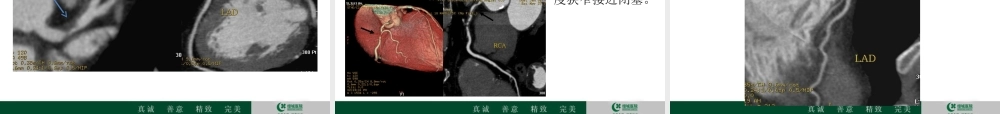

冠心病的CT检查价值放射科邱金海冠心病是严重危害人们健康的疾病,在许多国家,冠心病死亡人数居总死亡数的首位,而且,多数心血管病死亡发生在创造力最高、对社会和家庭贡献最大的年龄组。对此,有关专家呼吁,不吸烟、平衡膳食、经常运动和良好的心态,是保持心脏健康的四大要素。许多的名人如著名相声演员马季、侯耀文,著名小品演员高秀敏,还有最近中国共产党优秀党员、发改委副主任姚作汀等都是被冠心病夺去了生命。冠状动脉粥样硬化性心脏病是冠状动脉血管发生动脉粥样硬化病变而引起血管腔狭窄或阻塞,造成心肌缺血、缺氧或坏死而导致的心脏病,常常被称为“冠心病”。放射影像上诊断冠心病的标准是冠状动脉血管管腔狭窄超过50%。冠心病定义流行病学冠心病的患病率城市为1.59%,农村为0.48%,合计为0.77%,呈上升趋势。冠心病在美国和许多发达国家排在死亡原因的第一位。然而,美国从20世纪60年代开始,出现冠心病死亡率下降趋势。得益于60-80年代美国所进行的降低冠心病危险因素的努力,主要是控制危险因素和改进心肌梗死的治疗。2009年中国城市居民冠心病死亡粗率为94.96/10万,农村为71.27/10万,城市高于农村,男性高于女性。危险因素与诱因冠心病的危险因素包括可改变的危险因素和不可改变的危险因素。了解并干预危险因素有助于冠心病的防治。可改变的危险因素有:高血压,血脂异常(总胆固醇过高或低密度脂蛋白胆固醇过高、甘油三酯过高、高密度脂蛋白胆固醇过低)、超重/肥胖、高血糖/糖尿病,不良生活方式包括吸烟、不合理膳食(高脂肪、高胆固醇、高热量等)、缺少体力活动、过量饮酒,以及社会心理因素。不可改变的危险因素有:性别、年龄、家族史。此外,与感染有关,如巨细胞病毒、肺炎衣原体、幽门螺杆菌等。冠心病的发作常常与季节变化、情绪激动、体力活动增加、饱食、大量吸烟和饮酒等有关。症状•胸痛(心绞痛)•胸闷•心悸•呼吸困难•冠心病的主要临床表现有三种:心绞痛、心肌梗死和心性猝死。冠心病猝死的病理过程是,在冠状动脉硬化和心肌缺血的基础上,突然发生心脏骤停。猝死发生时如有旁人在场,应抓紧时间及时实施心肺复苏等抢救措施。如何来预防冠心病?检查方法•心电图•心电图负荷试验•动态心电图•核素心肌显像•超声心动图•血液学检查•冠状动脉CT•冠状动脉造影及血管内成像技术为什么要做CT,CT能解决什么问题?简介CT心脏冠状动脉成像在冠状动脉斑块的研究、冠心病、急性冠脉综合症及其它冠状动脉病变...